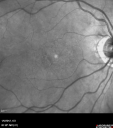

OD: Vertical C/D ratio is 0.0. There is posterior vitreous separation. There is a bull’s eye pigment irregularity in the macula.

OS: Vertical C/D ratio is 0.1. There is posterior vitreous separation. There is a mild bull’s eye pigment irregularity in the macula.

Plaquenil Toxicity both Eyes - Partial Bull's Eye - Discontinued 6 Years ago 1478 views82-year-old woman was on Plaquenil from 1976 from 2005, 200 mg a day. It was discontinued because of abnormal visual fields 6 years ago. OD 20/32, OS 20/40     (0 votes)